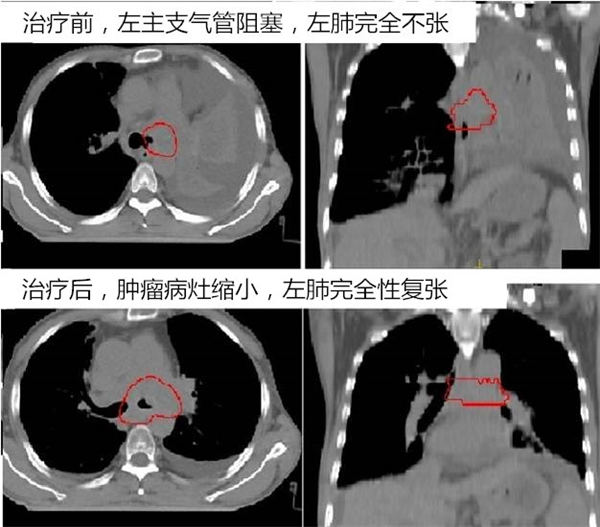

北京燕化医院一位60多岁的肿瘤者王先生(化名),因左肺恶性肿瘤导致左全肺不张,导致身体多处脏器损伤。

准备放弃治疗之际,听闻北京燕化医院新开了放疗科,后听放疗科夏火生主任介绍:放疗可以使他的肺重新张开。王先生及家人决定用放射治疗试试,在经过放疗科经心治疗,仅仅照射4次后,王先生的肺就张开了,又一次点燃了他对生命的希望……